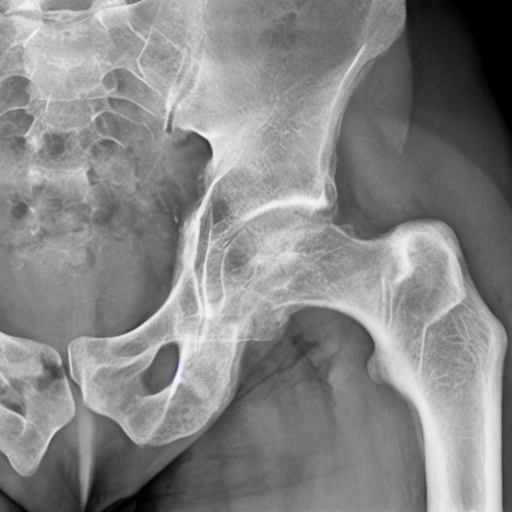

1. Showing the subtrochanteric fracture in the porotic bone.

protic bone